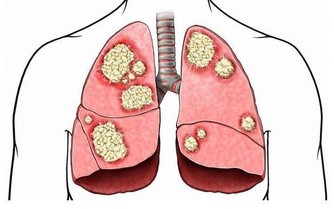

1. 稀釋胃液

我們的胃會分泌胃酸,用來消化和分解食物。除此之外,這些液體還負責殺死可能與食物一起攝入的任何傳染因子。另外,胃中的消化酶對我們的整體健康至關重要,因為它們能讓胃收縮,並研磨我們吃的食物。當酶被水稀釋時,它不僅會使整個系統的消化功能受影響,而且可能會導致一些人腸壁痙攣。整個消化過程的這種停滯,使得食物在胃中停留的時間更長,並且減緩了食物進入小腸以吸收營養物質的過程。

我們的胃有一種“知道什麼時候你會吃東西,並立即開始釋放消化液”的本領,如果你吃東西的同時喝水,實際上是在稀釋消化液,從而阻止它們分解食物。